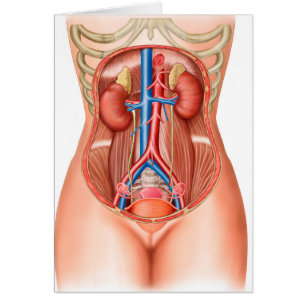

Anatomi hos kvinnlig kropp med reproduktionsorgan hälsningskort

Försäljningspris 49,00 kr. Ursprungligt pris 54,00 kr.